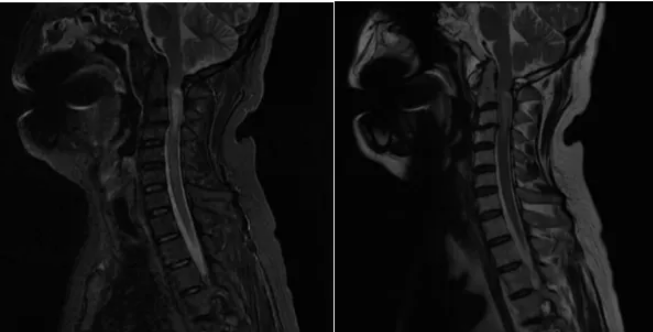

颈髓平扫示:C2-4水平颈髓内见片状稍长T1、T2、高STIR信号,长约3cm。

颈髓增强扫描示:C2-4颈髓病变增强扫描病变上缘见斑片状明显强化,边界欠清。